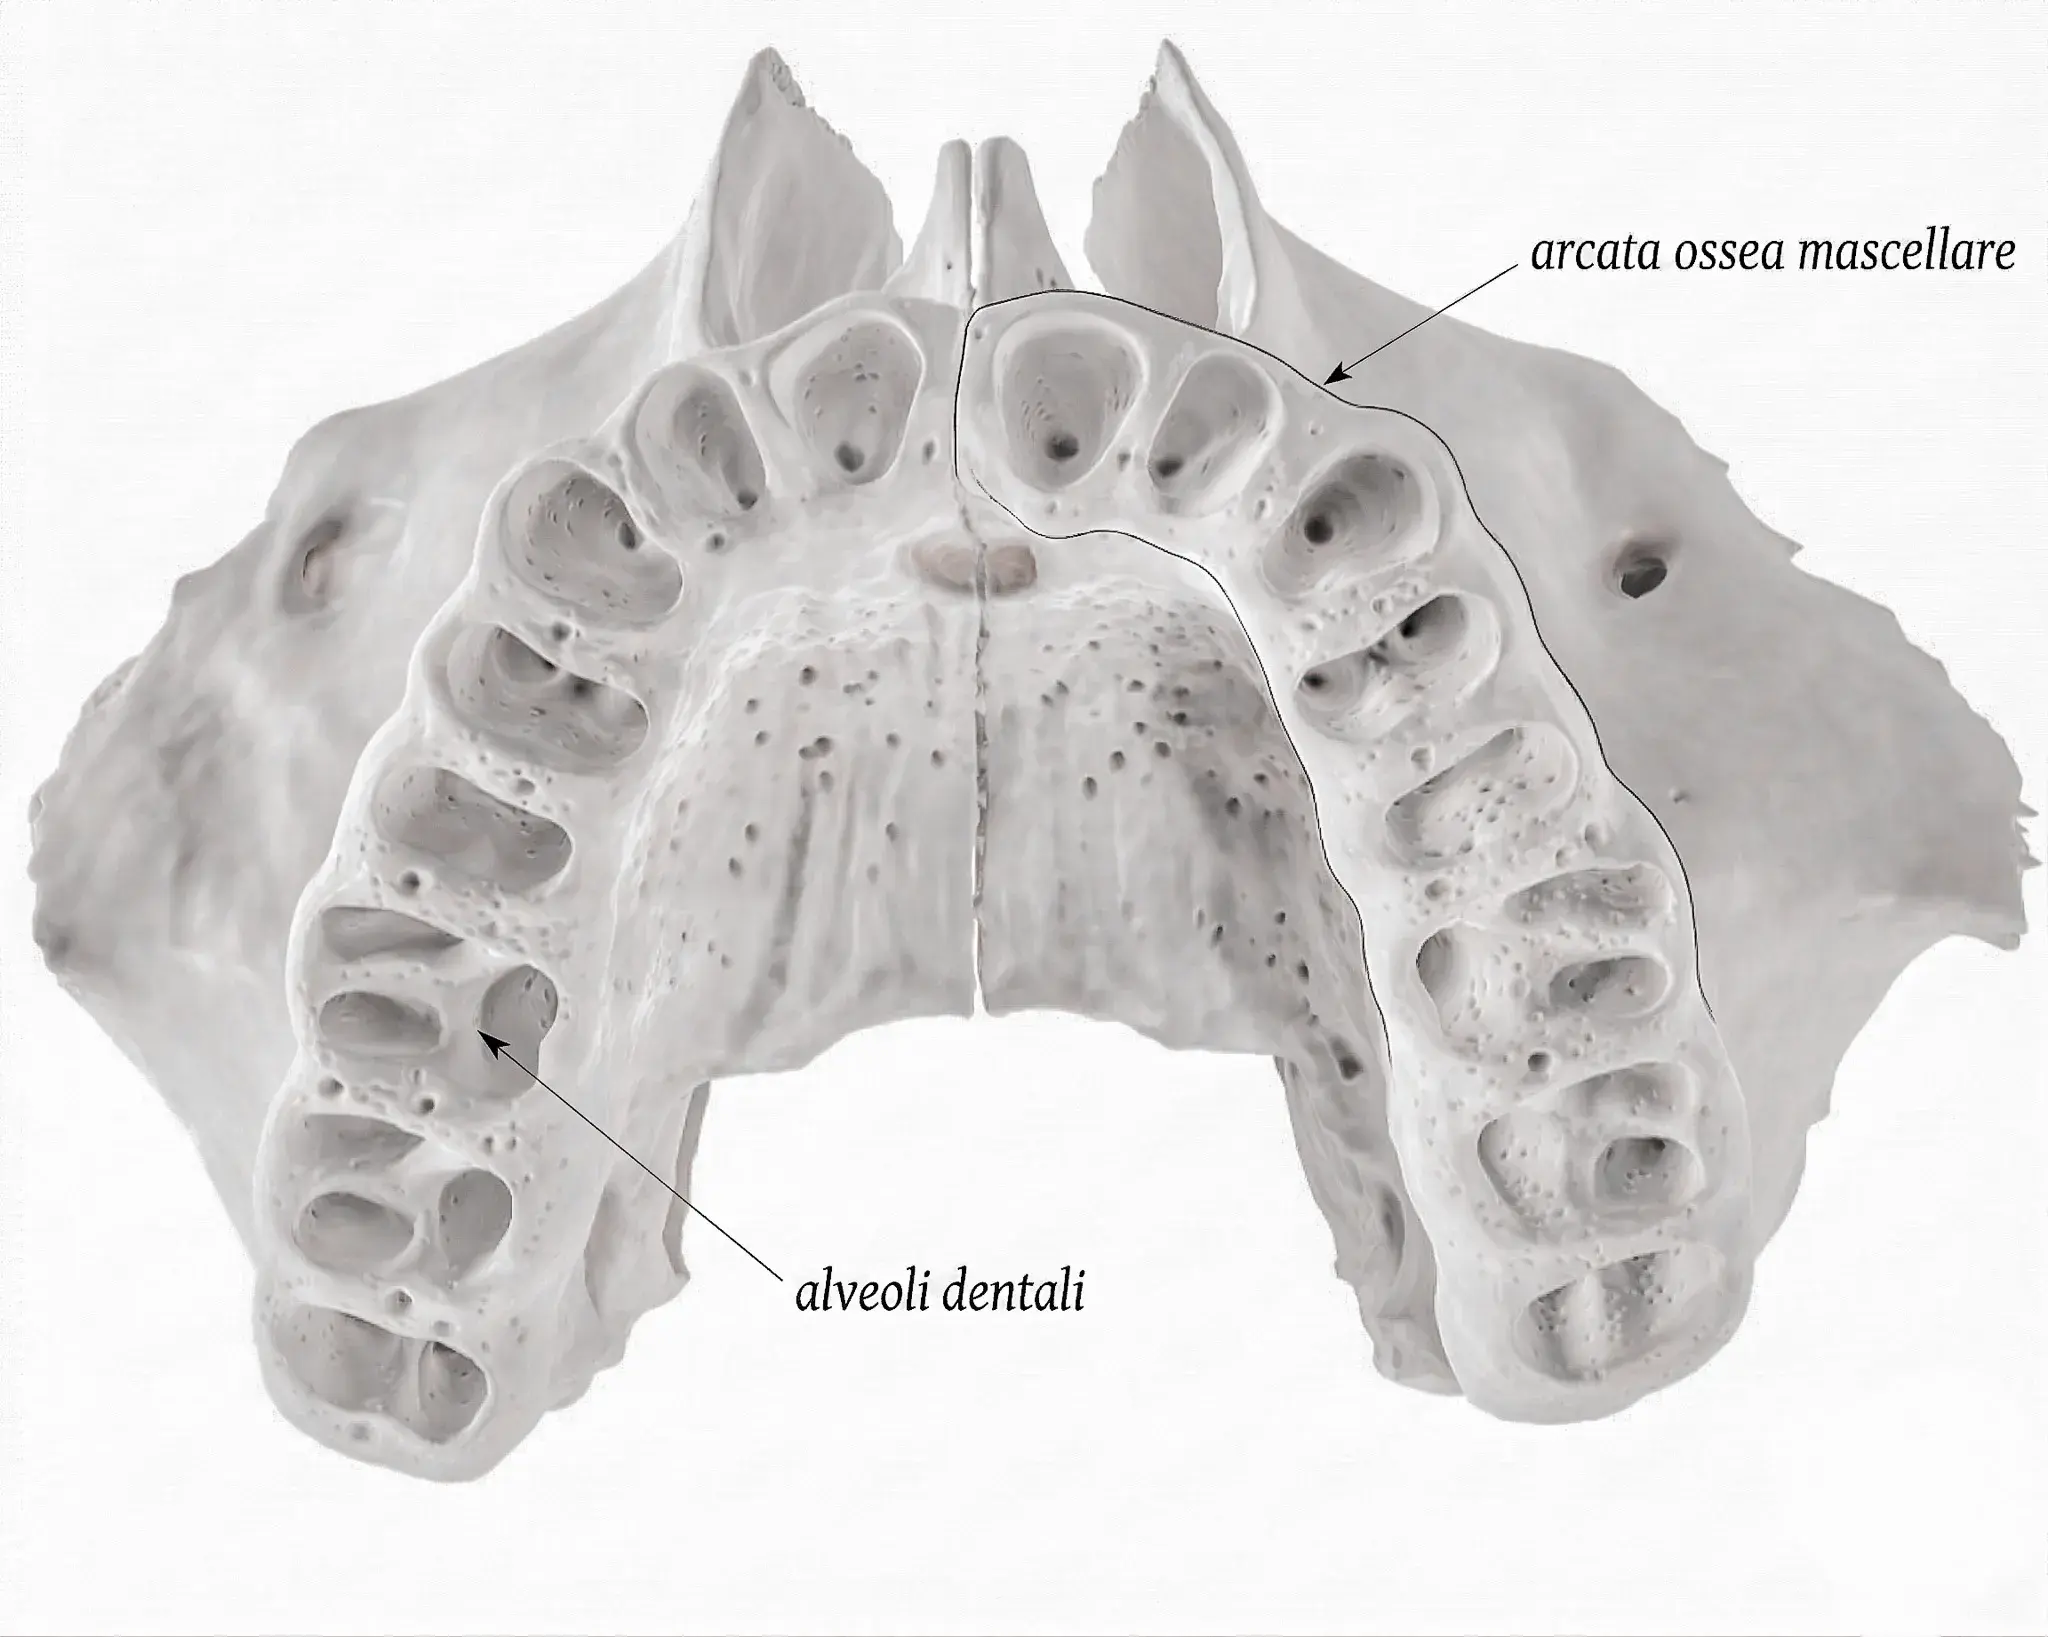

Le ossa con gli alveoli sono mascella e mandibola — le uniche che tengono in piedi i denti. Cosa succede quando perdi un dente e come si preserva l'osso.

L'osso alveolare è la base dei tuoi denti e dei tuoi impianti. Quando manca, si rigenera. Anatomia, cause di riassorbimento e soluzioni.